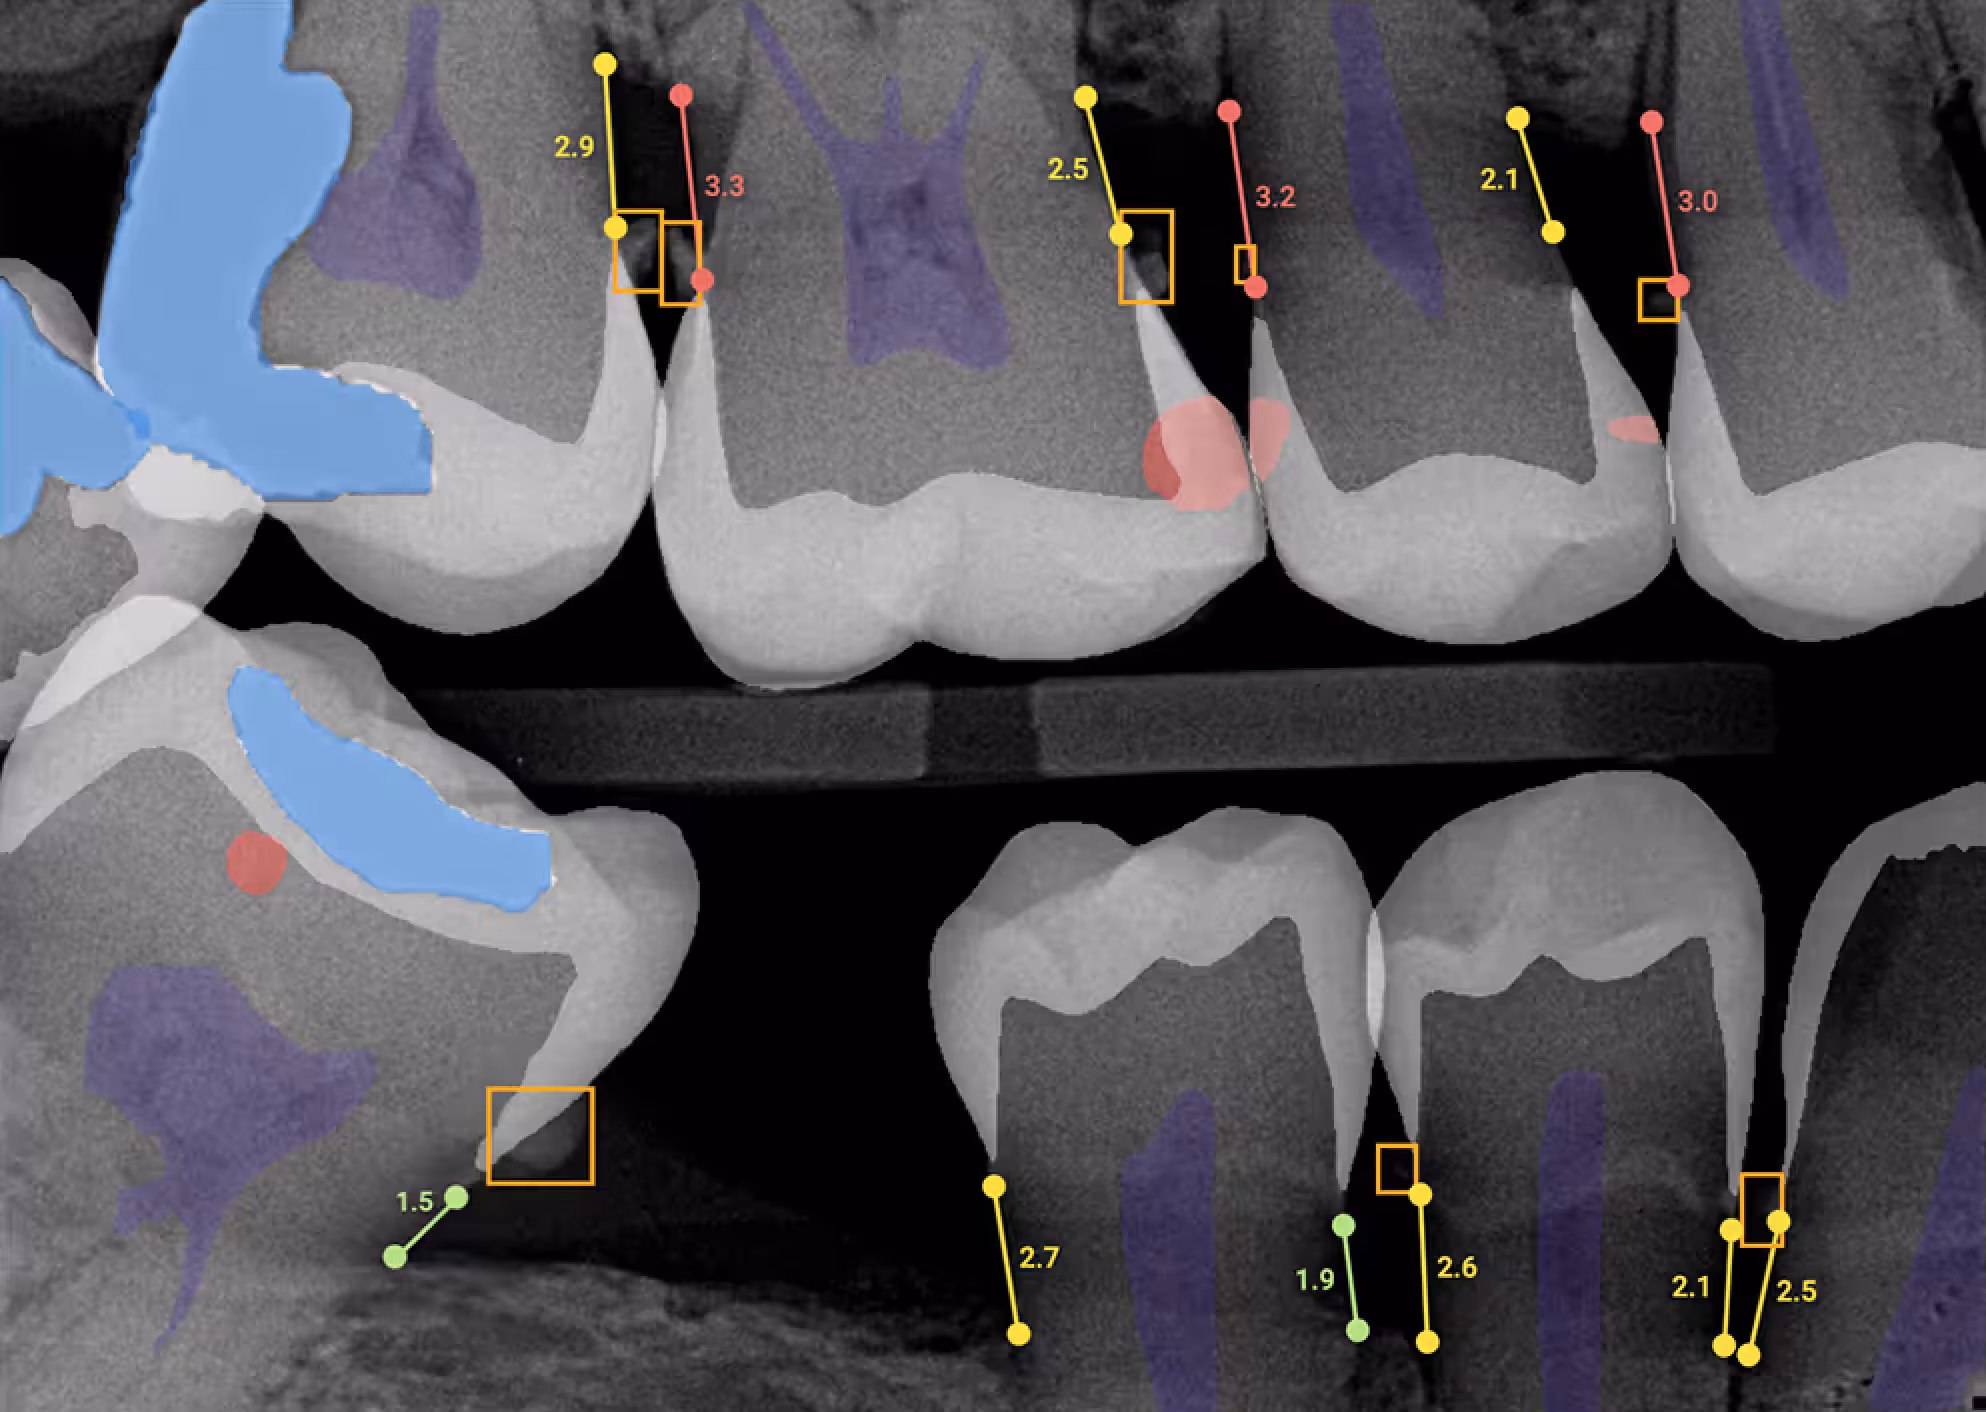

That’s why every comprehensive exam in our office is powered by Overjet, an FDA-cleared artificial intelligence technology that enhances X-ray interpretation and helps us identify the earliest signs of cavities or gum concerns — sometimes even before they’re visible to the eye.

This level of precision allows our doctors to act sooner, treat smaller, and protect more of your child’s natural tooth structure. The most preventative thing we can do is to stop a cavity from growing as soon as it starts — and Overjet helps us do exactly that.You can have peace of mind knowing that your child’s care is both proactive and truly preventative, guided by one of the most advanced dental technologies available today. We’re proud to be one of the only pediatric dental practices in the state using this FDA-cleared AI system to bring a new level of accuracy and confidence to your family’s care.

Teeth cleanings and oral exams are some of the most important parts of preventive dentistry at our office. Your child will come in and see one of our team members for a cleaning and check up at least every six months. We’ll clean away plaque and tartar from your child’s teeth, then one of our specialty trained dentists will perform a comprehensive exam to make sure that their teeth, tongue, and gums are strong and healthy. This oral exam also includes an essential head and neck cancer screening and any necessary x-rays that are needed to diagnose cavities or possible infections. We even use AI-powered second opinions to evaluate images, which can catch issues that are otherwise invisible to the naked eye. The doctor will discuss their findings with you and let you know if your child might need any additional dental treatment, and all safe and reasonable options to do so.